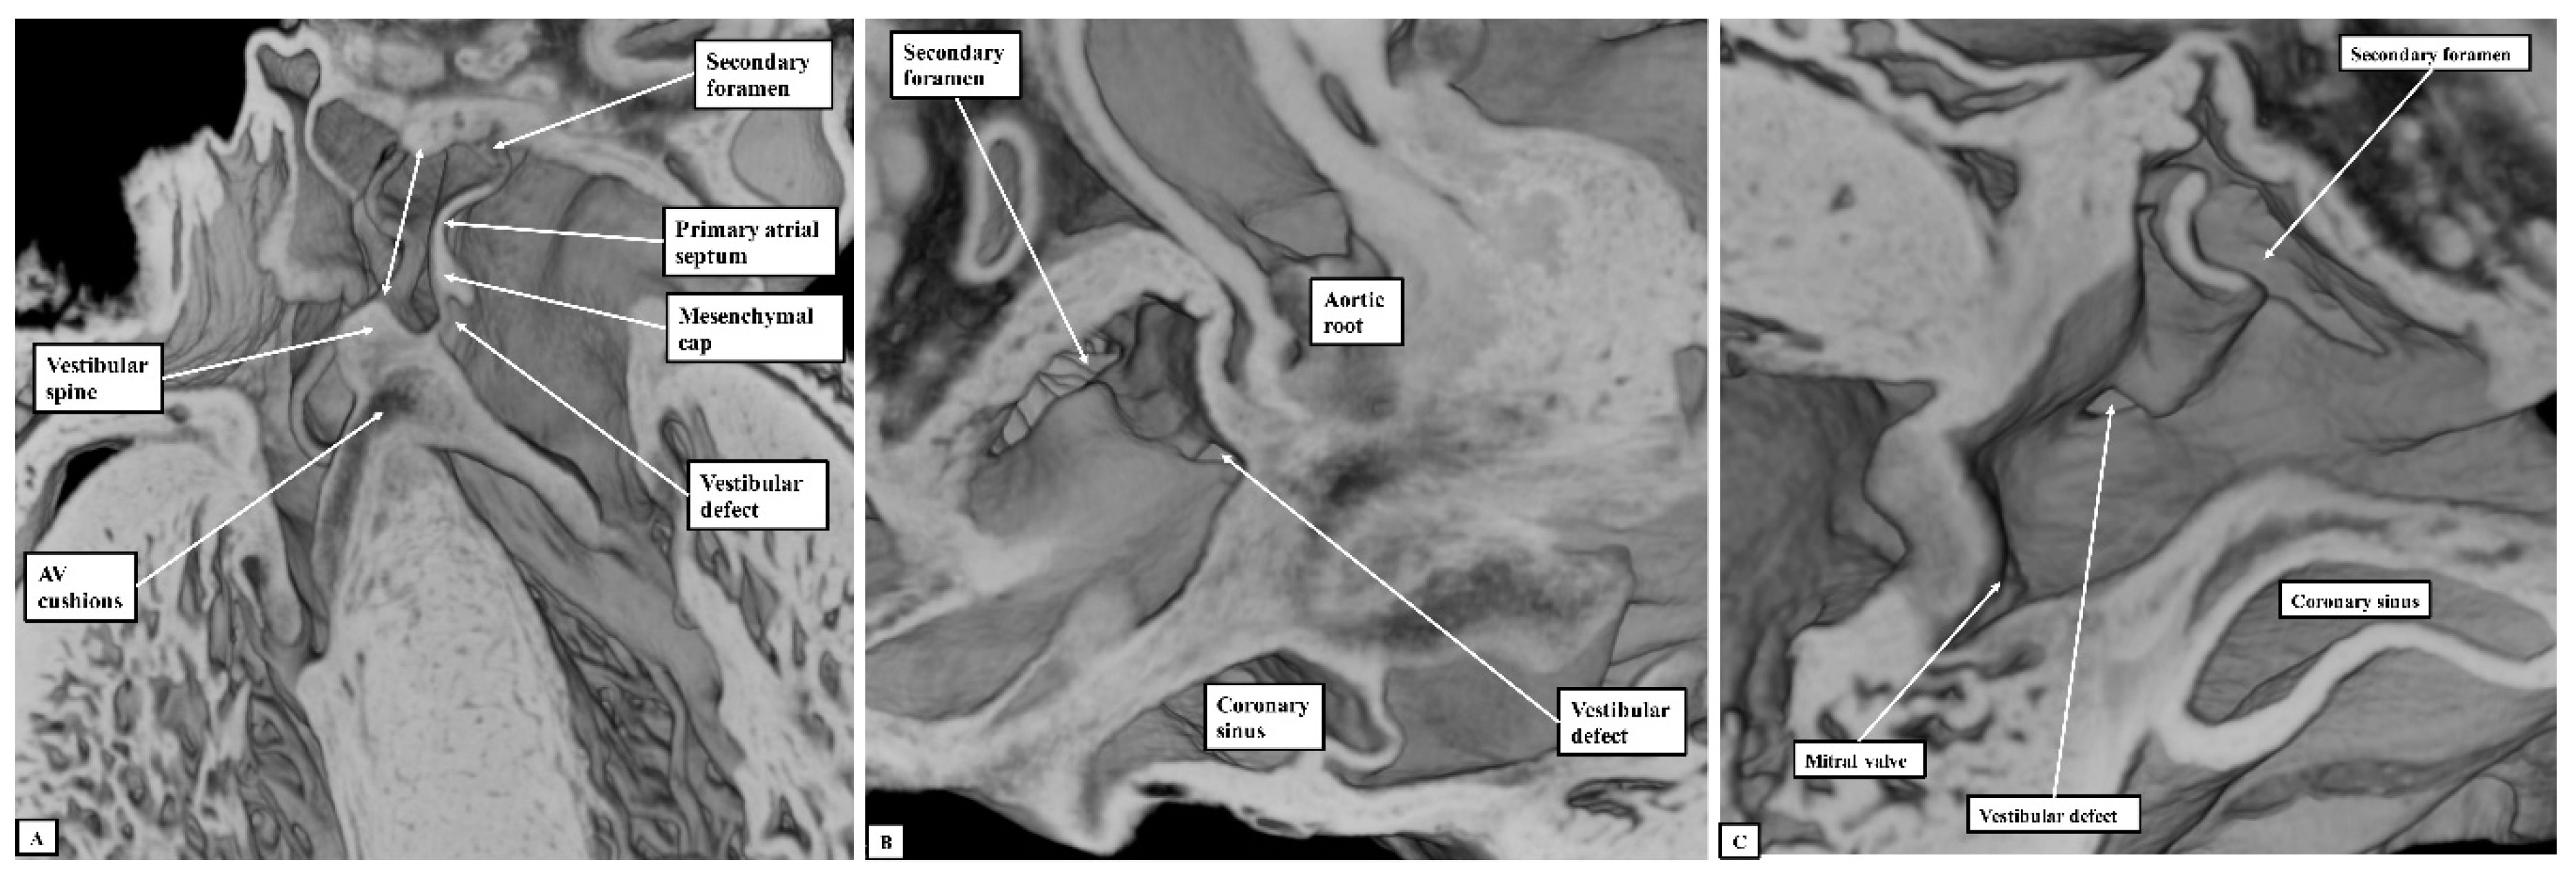

If development proceeds in a normal fashion, the margins of the oval fossa are intact by E15.5. We examined episcopic datasets prepared from 48 mouse embryos at this stage. In 38 of the mice, the findings show the normal arrangement, with the primary septum folded on itself cranially, its length being considerably greater than the length of the fossa (Figure 6A). In these 38 datasets, the vestibular spine and mesenchymal cap fused together to form the caudal rim of the fossa, with obliteration of the seam initially seen between the two components during E13.5 (Figure 5D). The primary septum now forms the floor of the oval fossa, with the space between its cranial margin and the atrial roof forming the oval foramen, or secondary atrial foramen. The excessive length of the septum relative to the dimensions of the fossa provides the mechanism that permits closure of the foramen subsequent to birth. In 10 of the datasets prepared from mice sacrificed at E15.5, however, we found deficiencies of either the inferior rim of the oval fossa, or the attachment of the leading edge of the primary septum. In two, the findings could be attributed to the failure of formation of the vestibular spine (Figure 6B), with additional failure of growth of the primary septum in one of the two. In both, the lack of growth of the spine was associated with persistence of a common atrioventricular junction, with the atrioventricular cushions fused to each other, and also to the crest of the muscular ventricular septum, in other words producing an “ostium primum” defect. In four further datasets, although the vestibular spine had protruded in anticipated fashion to form the caudal margin of the oval fossa, thus separating the right and left atrioventricular junctions and forming the caudal rim of the fossa, the primary septum itself was deficient adjacent to the caudal rim, thus producing a hole in the floor of the fossa adjacent to its antero-inferior buttress, in other words, an “ostium secundum” defect (Figure 6C) The defect was large in two of the datasets but smaller in the remaining two. In the remaining four datasets, the mesenchymal cap had failed to fuse with the vestibular spine. The spaces in the floor of the oval fossa in these four hearts (Figure 7), therefore, are directly comparable to the vestibular defects found in our autopsied hearts.

Figure 7. The images show the features of the vestibular defect, as was found in four of the datasets. The dataset used to prepare the figure is sectioned so as to show the appearance of the defect in the four-chamber plane (Panel A), and as seen from the right (Panel B) and left (Panel C) sides. The double-headed white arrow in the left-hand panel shows the margins of the oval fossa. AV—Atrioventricular.